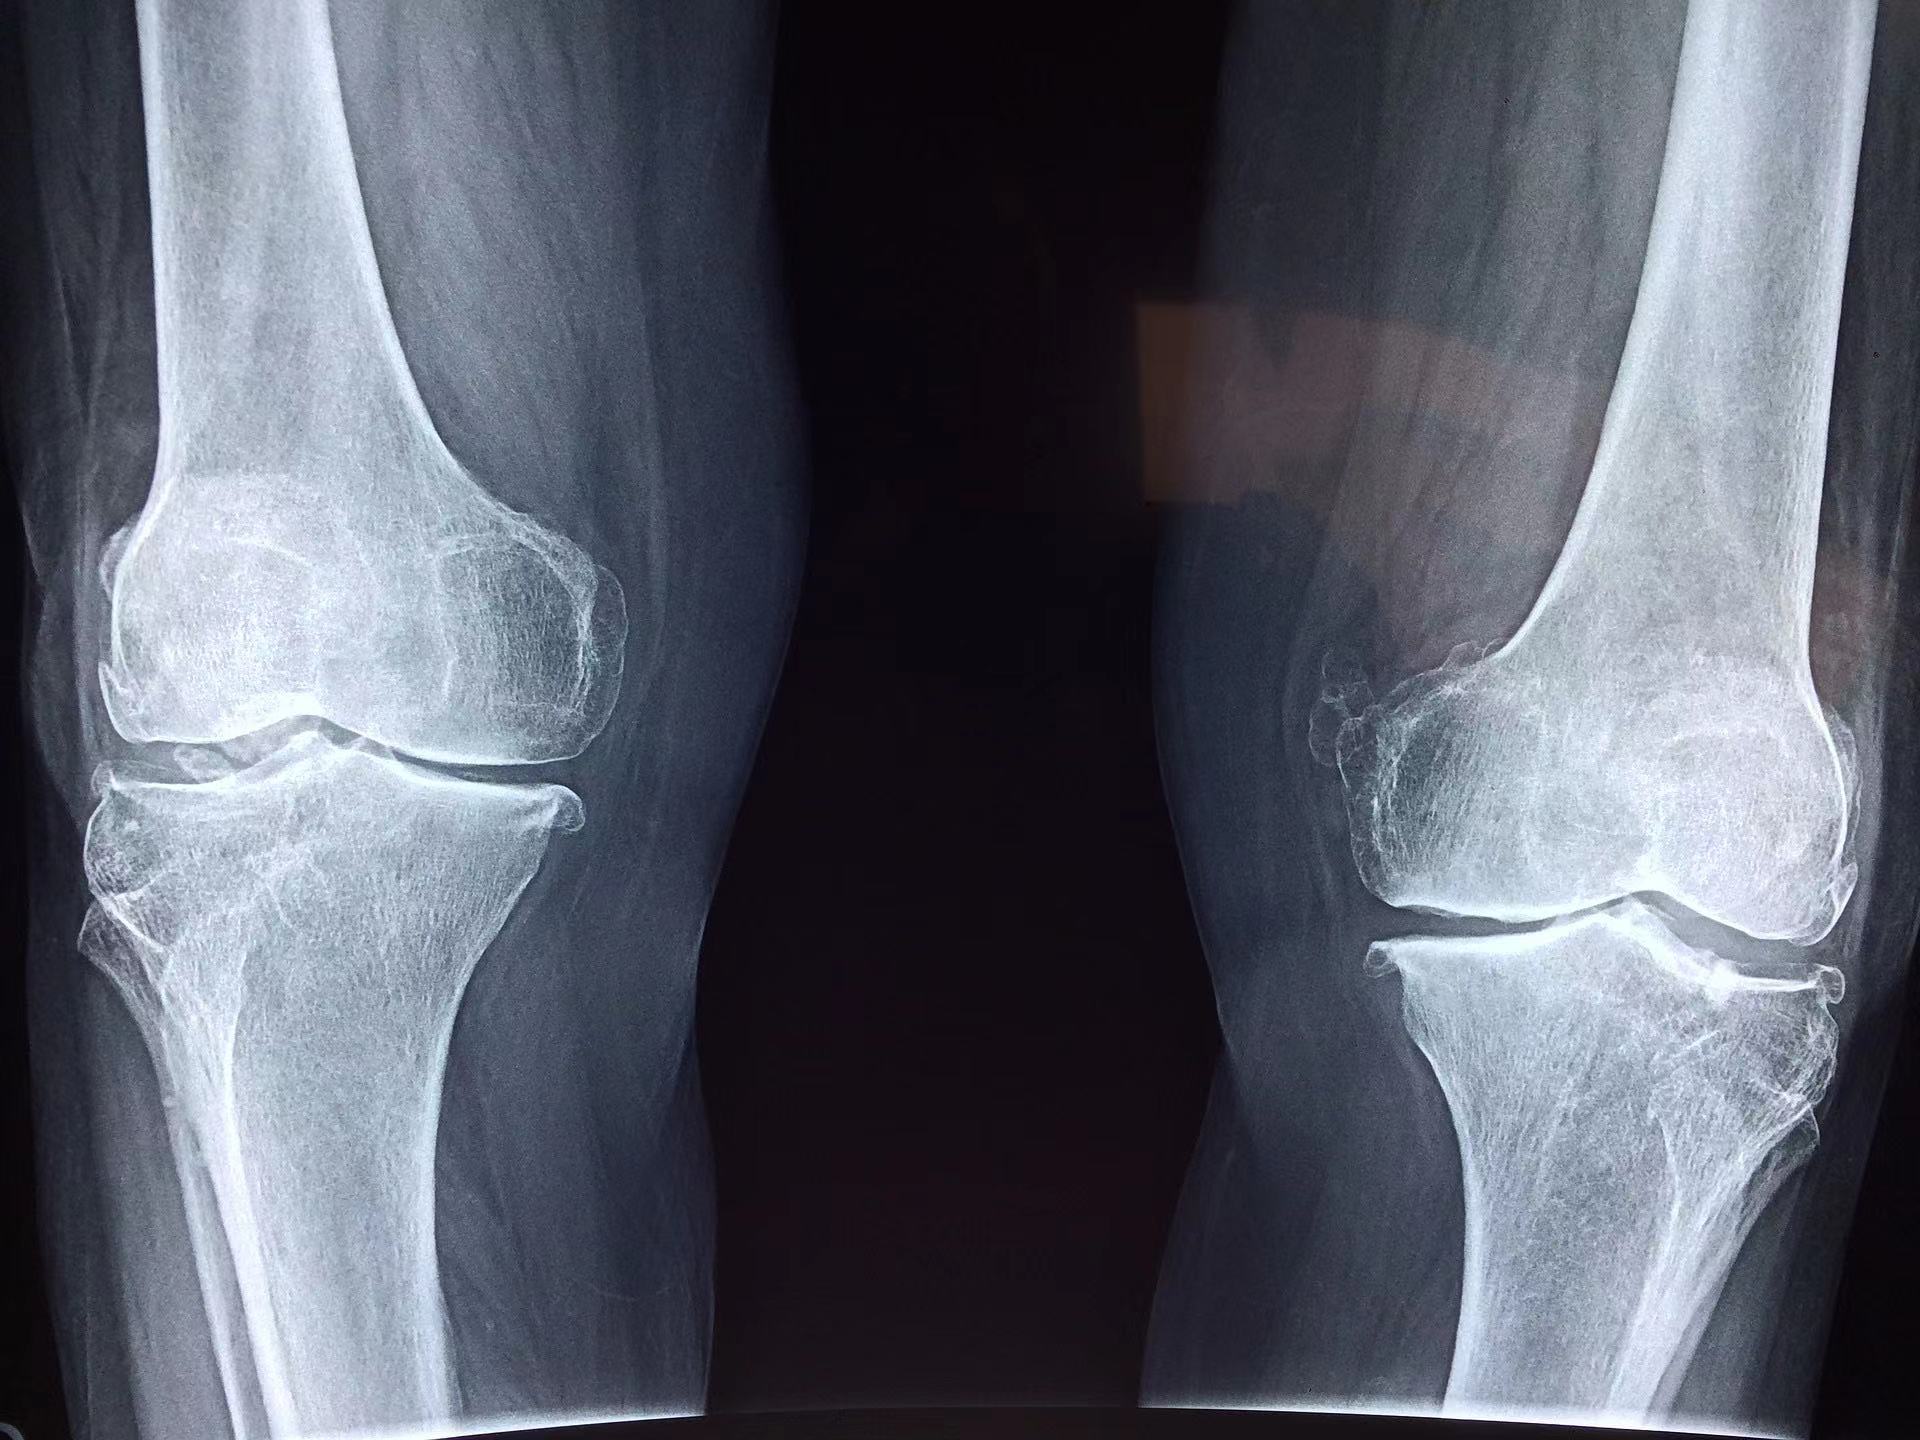

图片来自:Pixabay